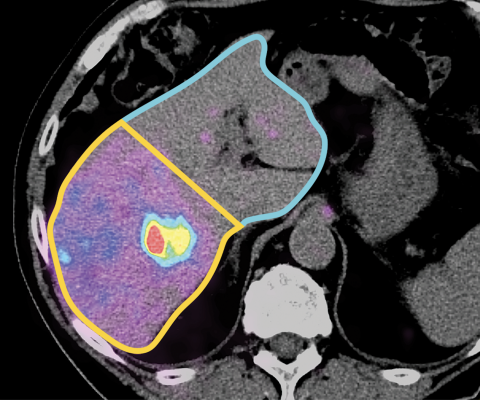

Oncology: MIM Software's clinical tools – paired with GE HealthCare's imaging solutions – bring improved flexibility, automation, and efficiency to clinicians. This includes more streamlined processing, structured reporting, fast and high-quality contouring, advanced image fusion, dosimetry capabilities, easier IT integration, and remote access – helping to boost healthcare productivity and promote personalized patient care.

There is also special focus on radiation therapy and Theranostics.

Radiation therapy – a type of treatment given alone or in combination with surgery and/or chemotherapy – is administered to nearly two-thirds of all cancer patients.i The addition of MIM Software’s radiation oncology solutions to GE HealthCare’s portfolio is designed to provide clinicians with complementary interoperable solutions that can help simplify complex planning, delivering high quality while helping to reduce time to treatment.

In Theranostics, the combined portfolio aims to enhance medical research and clinical workflows to help clinicians improve patient stratification and selection, response prediction, and support the development of new treatments, including alpha therapies.